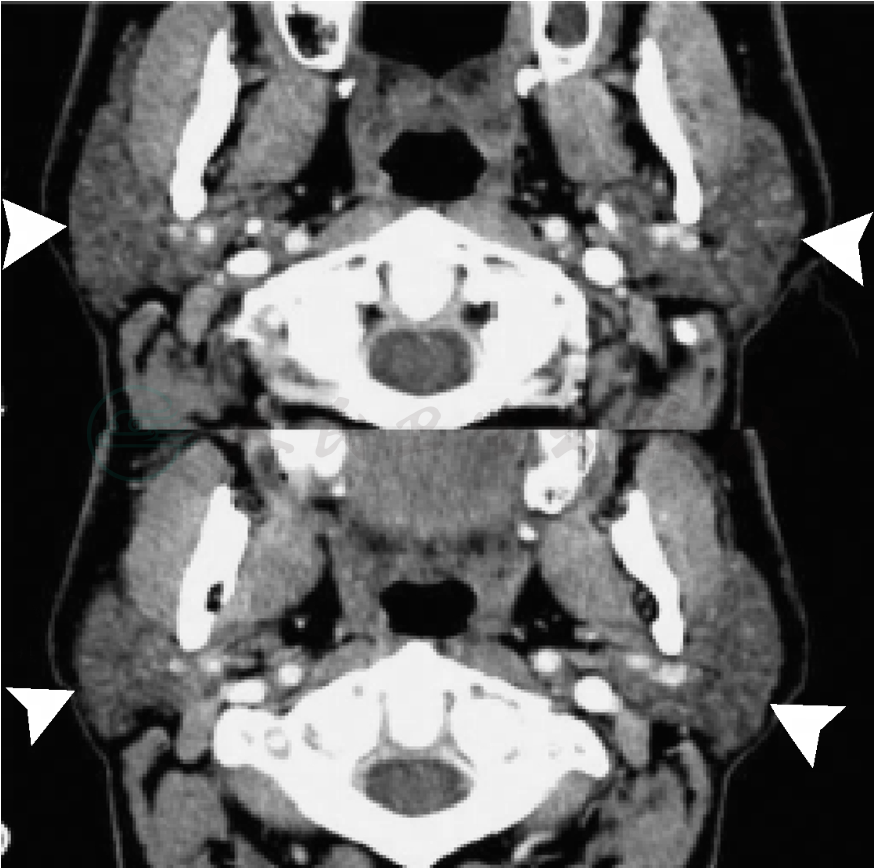

腮腺CT检查均可见腮腺弥漫增大表现,CT增强后可见不均匀强化表现,可有多发小低密度灶(图3)。MRI上可表现为腮腺弥漫增大,亦可表现为腮腺多发结节浸润影,在T1相和DWI相均有强化表现。同时,MRI还可见到面神经强化表现(图4)。对合并颈部及纵隔淋巴结肿大、肺内病变等典型结节病表现的患者,颈部及胸部CT检查对诊断有所帮助,必要时可以行上述部位的淋巴结活检、CT引导下穿刺等明确诊断。

图3 Heerfordt综合征患者腮腺CT表现

可见腮腺弥漫肿大,不均匀强化,有小低密度灶等表现(箭头)